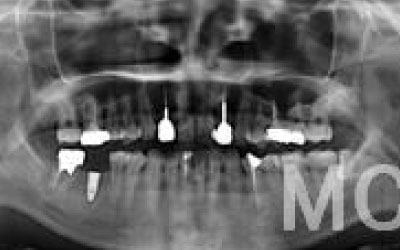

CTでは骨や歯の状態などを3次元で見ることができ、正確な距離を測ることも可能です。

骨の厚みや傾き、神経の位置などを事前にしっかり計測することで安全なインプラントが可能となります。